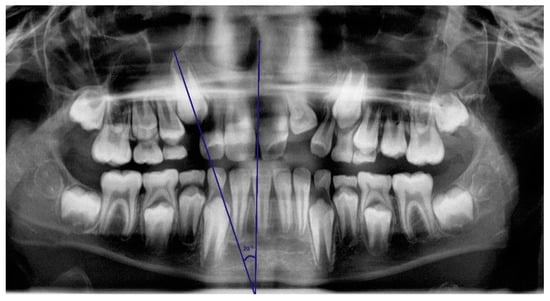

On panoramic radiographs taken at the age of 8–10 years, inclination angles of the unerupted maxillary canines were measured according to Westerlund’s recommendations. (Figure 1). The measurement was taken in the Ortomed Evo software with the use of a digital protractor tool between a long axis of the permanent unerupted canine and a vertical reference line within the median plane. The vertical line was drawn based on anatomical structures, such as the nasal septum and the median suture of the maxilla and mandible. The condition for the measurement was the presence of at least 1/3 root length. The angle was measured with an accuracy of 1°, and the measurement was taken by a trained researcher. Unerupted canines with an angle greater than 30° were qualified into the group with increased risk of impaction. Canines on both sides of the jaw were examined.

Figure 1. Angle of unerupted canine inclination was drawn through the long axis of the permanent maxillary canine and midsagittal vertical reference line.